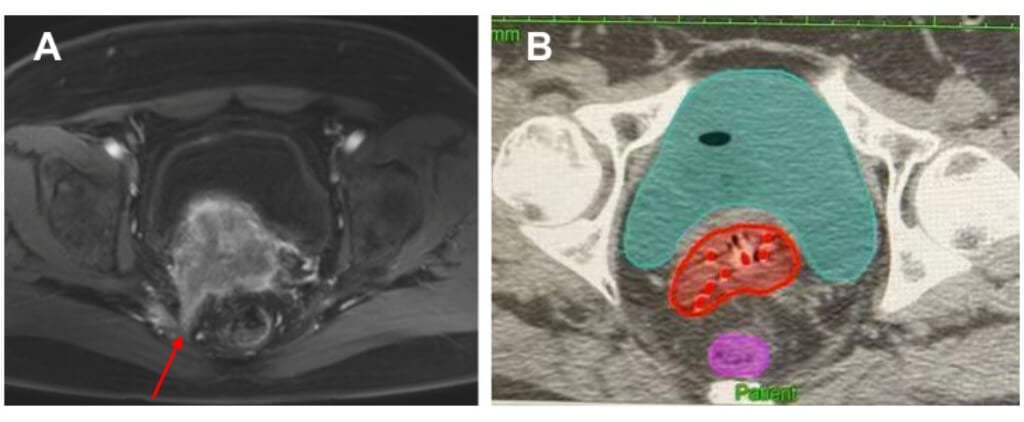

Before the start of internal radiation therapy, a detailed examination is carried out. Patients are subjected to pelvic MRI or CT scans, which enable specialists to see the cancer cells, define what size the tumor is, and where it is located precisely, as well as examine the state of other organs and healthy tissue. On the basis of these images, the treatment team develops a unique treatment plan. At this point, the radiation oncologist determines the best radiation dose and determines the type of applicator that should be used, whether it is an intracavitary brachytherapy or interstitial brachytherapy.

A major innovation is brachytherapy treatment guided by imaging. MRI or CT scans help locate the cancer cells precisely. This enables the treatment team and the radiation oncologist to come up with an individualized treatment plan that gives the best radiation dose to the tumor without necessarily sacrificing the surrounding organs.

Intracavitary brachytherapy and interstitial brachytherapy, planning with 3D software, are also used in modern clinics to enable a physician to customize treatment to the stage of cervix cancer and individual anatomy. In some cases, temporary brachytherapy or permanent brachytherapy is applied, offering flexible and individualized care.